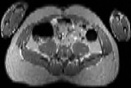

Visible Human male: Sectio transversalis 1749

CT

NMR

Pd                          / T2 \                         T1